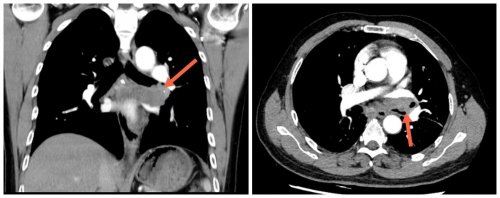

术前胸部CT

患者男性,50岁,确诊晚期肺腺癌(ALK阳性)8月余,经靶向治疗后病灶曾有吸收好转,4月18日因气喘进行性加重,再次收治市二院呼吸与危重症医学科综合病区。复查胸部CT和气管镜显示左肺门肿块突入左主支气管及左上、下叶支气管管腔,导致左主支气管管腔重度狭窄。如不积极给予处理,左主支气管一旦完全阻塞后,发生左全肺不张将加重患者呼吸困难,给后续治疗增加很大风险。